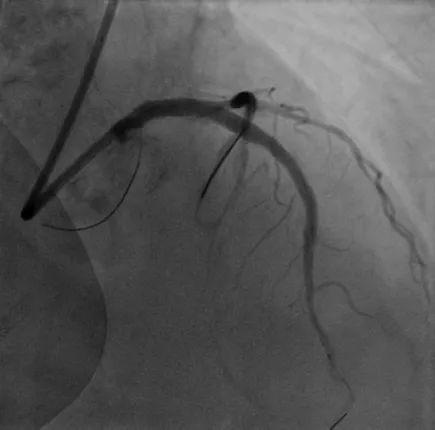

病例1

LAD长弥漫钙化病变:患者70岁男性,因间断胸痛3天入院,既往高血压病史、长期吸烟史,诊断不稳定型心绞痛。冠脉造影显示前降支近中段弥漫性狭窄伴钙化,应用冠脉腔内影像学技术-IVUS对该血管进一步评估,结果显示:前降支多处180-270°钙化,中段钙化结节(红色箭头所示)。顺利送入3.0*12mm Shockwave冲击波球囊至LAD中段,充盈4atm使球囊充分贴壁,显示球囊近段膨胀不良,随着冲击波能量释放,球囊逐渐扩张,膨胀扩张满意。先后对LAD多处钙化病变进行8个周期(80次脉冲)预处理,应用IVUS评估显示钙化处出现钙化断裂。该患者多处弥漫钙化病变,在IVUS指导下联合Shockwave冲击波球囊实现精准预处理,为后续支架植入奠定了基础。果然,送入长支架通过病变顺畅,释放扩张未感觉明显阻力即到位,支架膨胀舒展,成功植入支架。IVUS结果显示支架膨胀贴壁良好。

术前冠脉造影

植入支架后